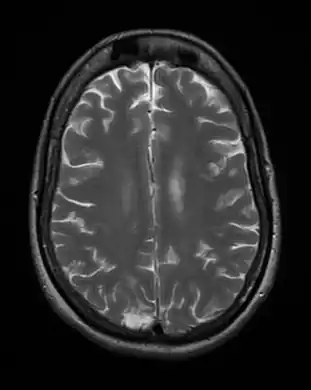

-

Cerebral toxoplasmosis (with primary involvement in the right occipital lobe) -

Cerebral toxoplasmosis -

Cerebral toxoplasmosis